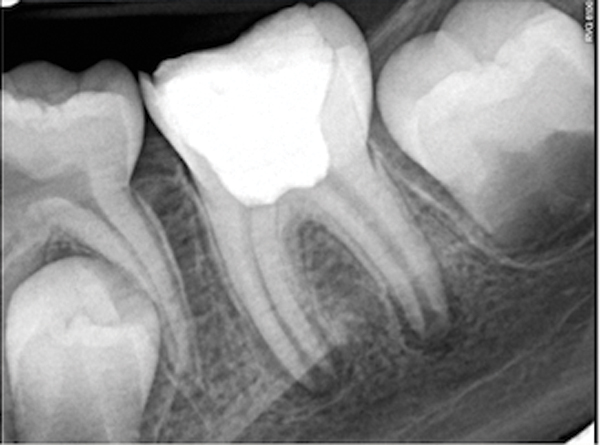

Fig 19. Preoperative radiograph of a case demonstrating apical periodontitis. Courtesy of Dr. Allen Ali Nasseh.

Fig 20. Immediate postoperative radiograph. Courtesy of Dr. Allen Ali Nasseh.

Fig 21. 5-year follow-up with complete healing. Courtesy of Dr. Allen Ali Nasseh.

This sealer solves most, if not all, of the previous problems of traditional sealers. Therefore, a thicker layer of sealer can be used because it is dimensionally stable and does not wash out. The core is used only as a hydraulic pump to move the sealer into place and allow for post space preparation or a pathway for retreatment. In addition and most importantly, the root canal preparation can be conservative and better adapted to restorative needs, since a traditional gutta-percha point (and not a metal plugger) is used to move the filling material. An additional benefit of the system is that there are now gutta-percha points that are impregnated with nano particles of bioceramics, so the sealer bonds not only to the root surface but also to the outer surface of the gutta-percha, eliminating the gap between the two (Figure 19 through Figure 21).